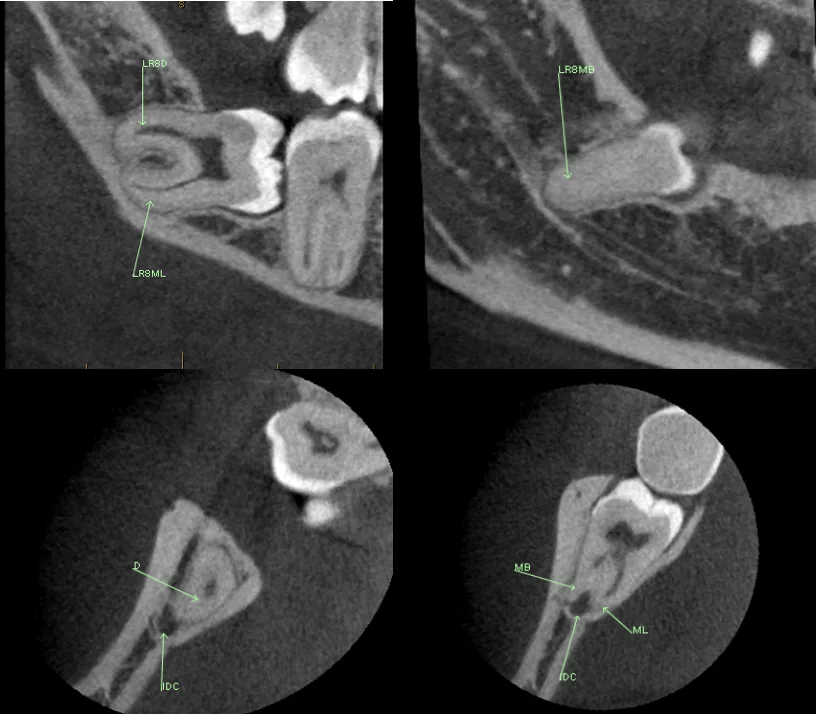

2. Key Image Capture™

• Innovative and proprietary algorithm

• Produces key images from dataset for impacted teeth applications

• Able to be manipulated, annotated and verified by the radiologist

• Report crafted using Report Wizard™

The Report Wizard™ code outputs the key images to further enhance the algorithm accuracy.

60027975173 021 F45 A6 2 D20 4 D53 AF24 FC3956 C4979 F